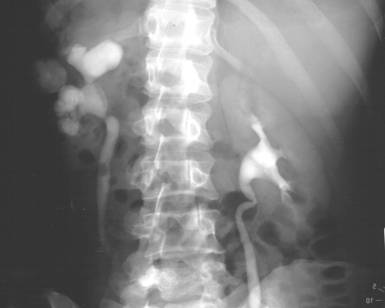

Fig. 59 – Megaureter stang